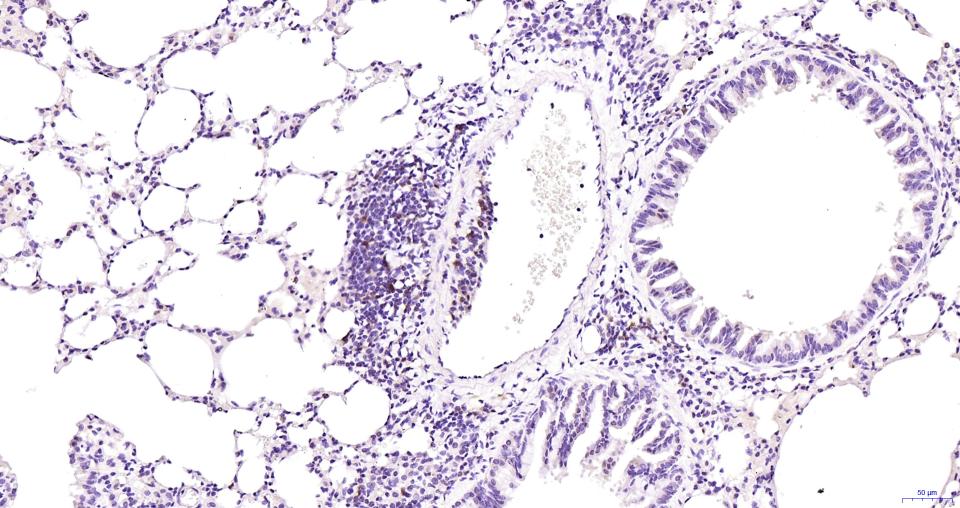

Paraformaldehyde-fixed, paraffin embedded Mouse Lung; Antigen retrieval by boiling in sodium citrate buffer (pH6.0) for 15 min; Antibody incubation with Cleaved-Caspase 3 p17 Monoclonal Antibody, Unconjugated(bsm-61090R) at 1:100 overnight at 4°C, followed by conjugation to the SP Kit (Rabbit, SP-0023) and DAB (C-0010) staining.